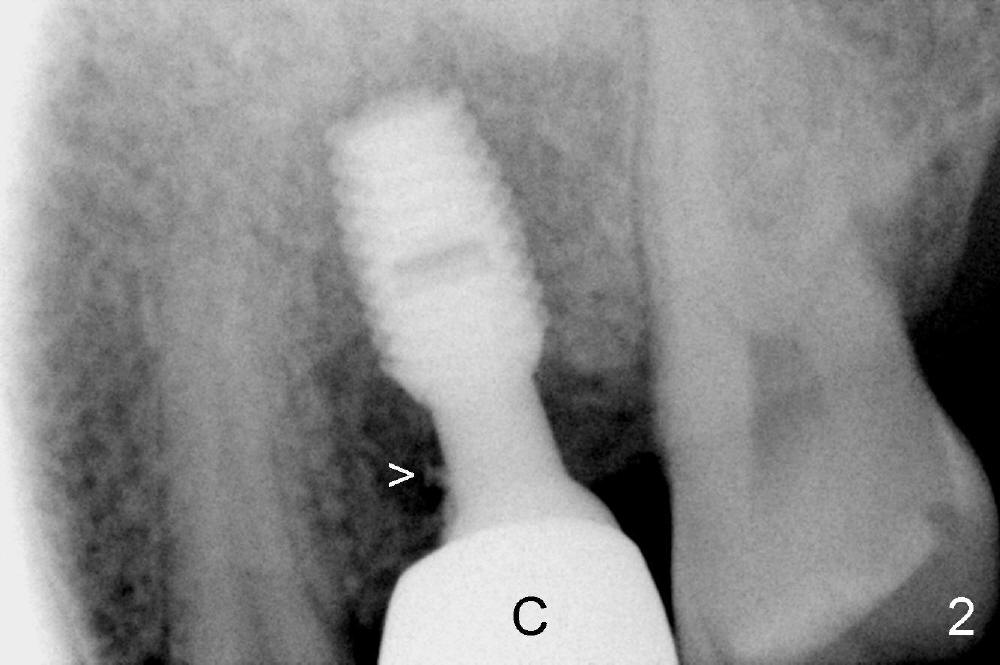

An offset shouldered abutment is inserted to an osteointegrated implant (Fig.1: A). Excess cement (Fig.2 >) is detected following intra-oral cementation of a Zirconia crown (C). The crown/abutment unit has to be removed from the implant (Fig.3). Fig.4 shows the crown/abutment unit with excess cement removed.